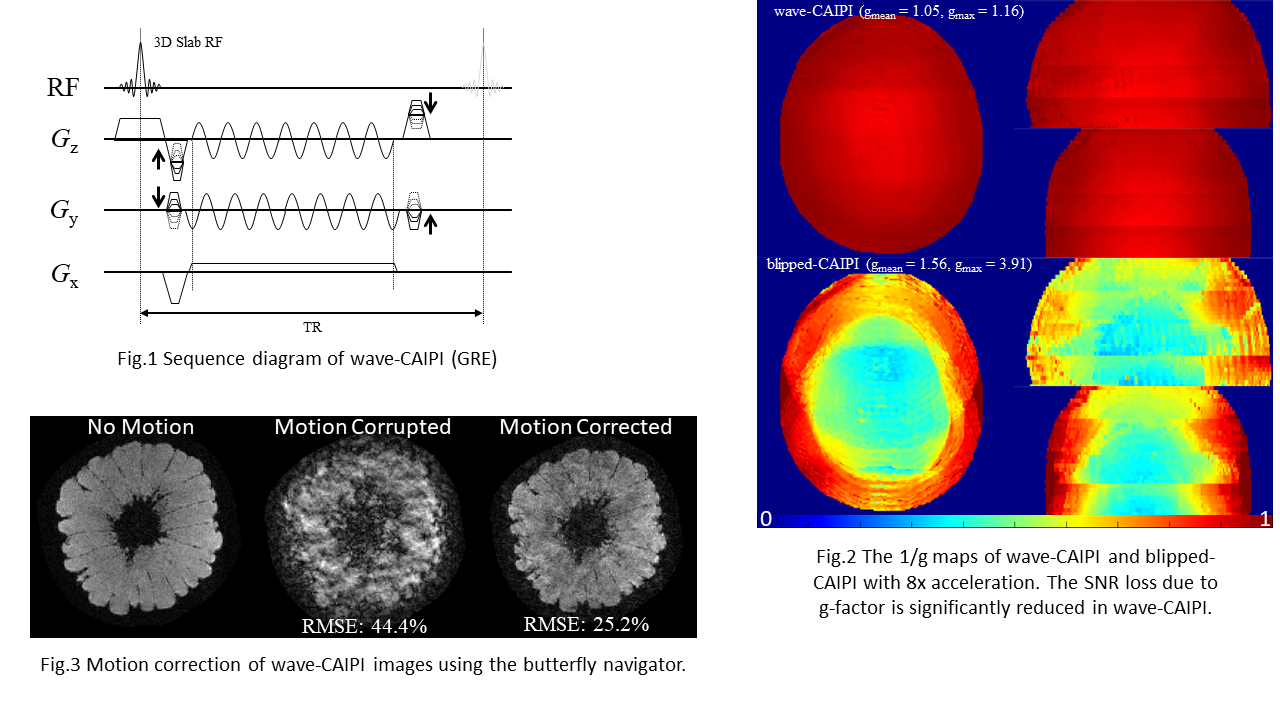

Magnetic resonance imaging (MRI) offers a unique opportunity to non-invasively study the human brain, equipped with a wealth of contrasts (to disentangle structures and functions), and a favourable window of spatiotemporal resolution. But to expand its clinical and neuroscientific scope, MRI has to become faster and more robust. A key ingredient to this end is a mechanistic understanding of the imaging physics, and its consideration in the way we acquire and reconstruct MR images. This comprises the choice of optimal sequence and sampling strategy for the target application (e.g., spiral trajectories for short echo-time) a detailed characterization of both hardware imperfections (e.g., heating/field drift and trajectory errors) and subject-related noise sources (e.g., breathing, motion) giving rise to image artifacts, the accurate inclusion of this information into an expanded signal model of the MR imaging process and advanced image reconstruction techniques capable of inverting these intricate models. This integrated approach leads to better imaging data tailored to the analysis and diagnostic purpose of the MR exams. The characterization of each scan’s imaging peculiarities allows for better comparability of multi-site studies in the era of big data. At the other end of the spectrum, personalized medicine requires individualized MR imaging protocols that are enabled by flexible and extendable signal models and reconstructions.